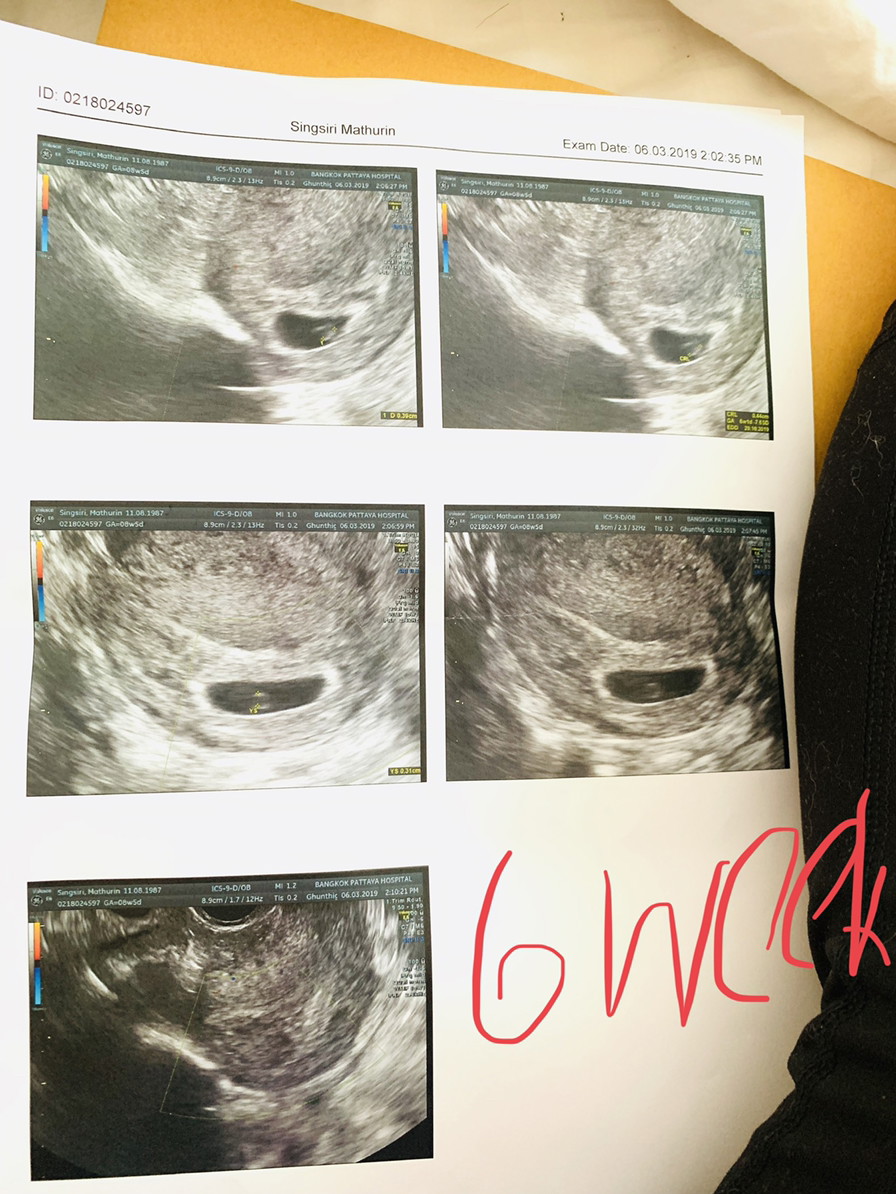

นี่ฝากตอน6wค่ะยังไม่เห็นเป็นตัว แต่เห็นหัวใจเต้นละค่ะ

นี่6w ค่ะหมอบอกเห็นชัดมาก หัวใจเต้นแล้วด้วย